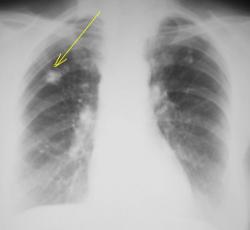

Уважаемые коллеги!. Какие будут мнения по поводу "тени", помеченной стрелкой. Пациент длительное время находился на учёте у фтизиатра.

2_vopros.JPG

Если на предыдущих снимках такая же каритнка, то туб изменения в фазе уплотнения. Если нет, то подозрительные спикулоподобные тяжи вселяют подозрения о наличии периферического рака зоне  постуберкулезных изменений или реактивации туб. процесса.

Можно согласиться с предидущим постом. Отложение извести (туберкулома?),но контуры какие-то нечёткие и тяжтстые. Для оценки динамики необходим R-архив.

Валентин Львович! Необходимо дифференцировать с периферическим раком и tbc в стации инфильтрации. Конечно же необходим рентгенархив (если таковой имеется).